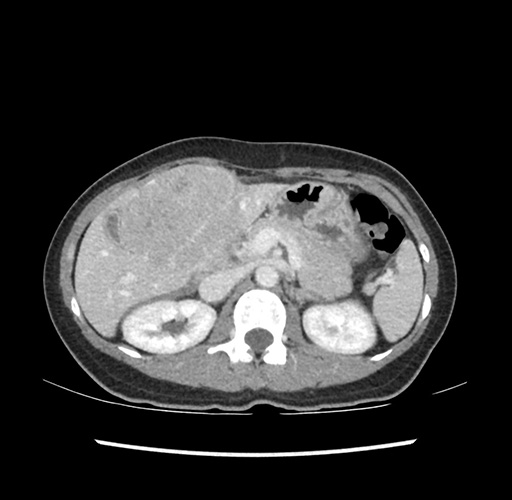

Imaging Analysis

Look through the patient's CT scan to identify any areas of concern for the necessary procedure.

Based on your CT findings, which issue(s) would give reason for "planned slowing down moment(s)" in this case?